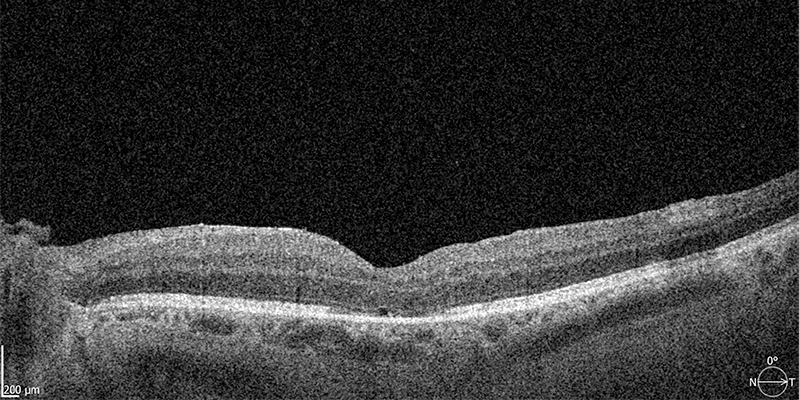

Mit der hochauflösenden optischen Kohärenztomographie (OCT) können wir die verschiedenen Netzhautschichten detailreich im Querschnitt sichtbar machen und das Makulaloch exakt darstellen. Auch die Größe des Makulalochs kann so ermittelt werden.

Optische Kohärenztomographie (OCT) – Vor der OP: Das Makulaloch ist deutlich zu erkennen (Pfeil)